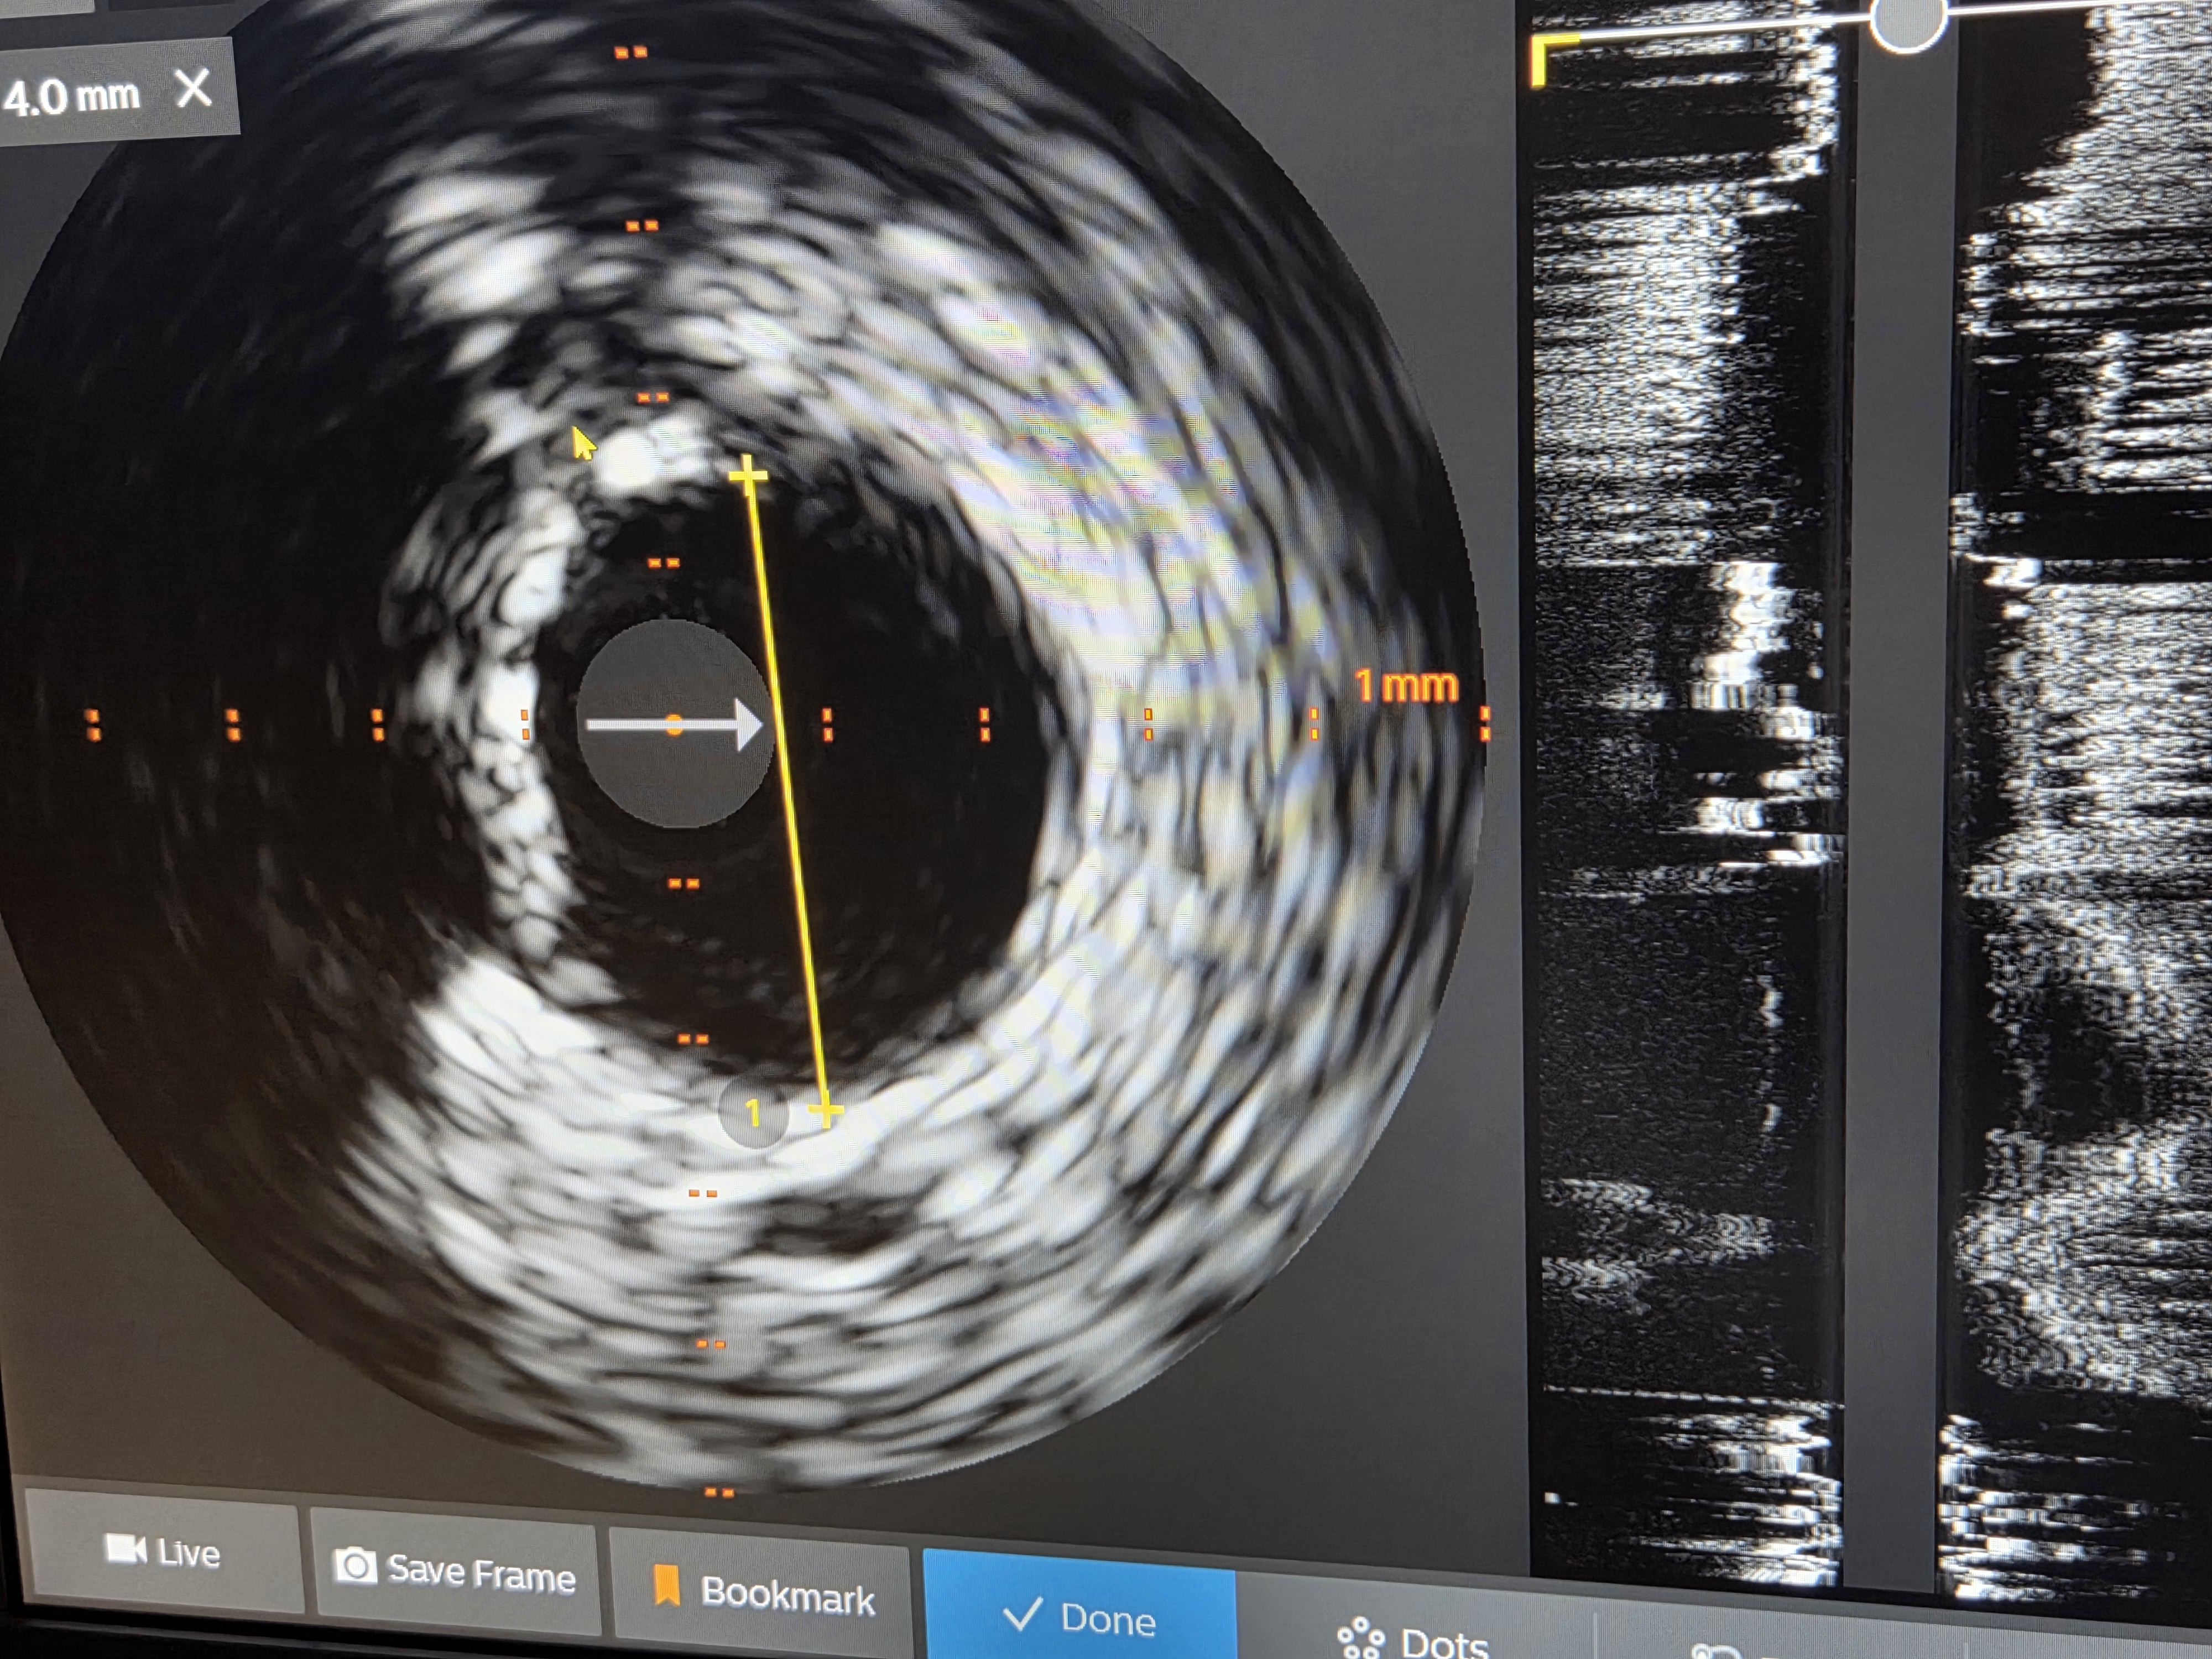

“Kod pacijentinje R.P. smo na koronarografiji verifikovali  tešku trosudovnu koronarnu bolest, pri čemu je desna koronarna artrija bila potpuno zapušena. Na lijevoj strani srca, u zoni glavnog stabla, suženja su iznosila oko 90 odsto, uz izraženu kalcifikaciju.. Odlučili smo se za revaskularizaciju putem stentova. Rađena je tehnika dva stenta u glavnom stablu. Obje artrije su uspješno sanirane. U sljedećem aktu će se otvarati ova hronično zapušena arterija,  objašnjava dr Janjičić.